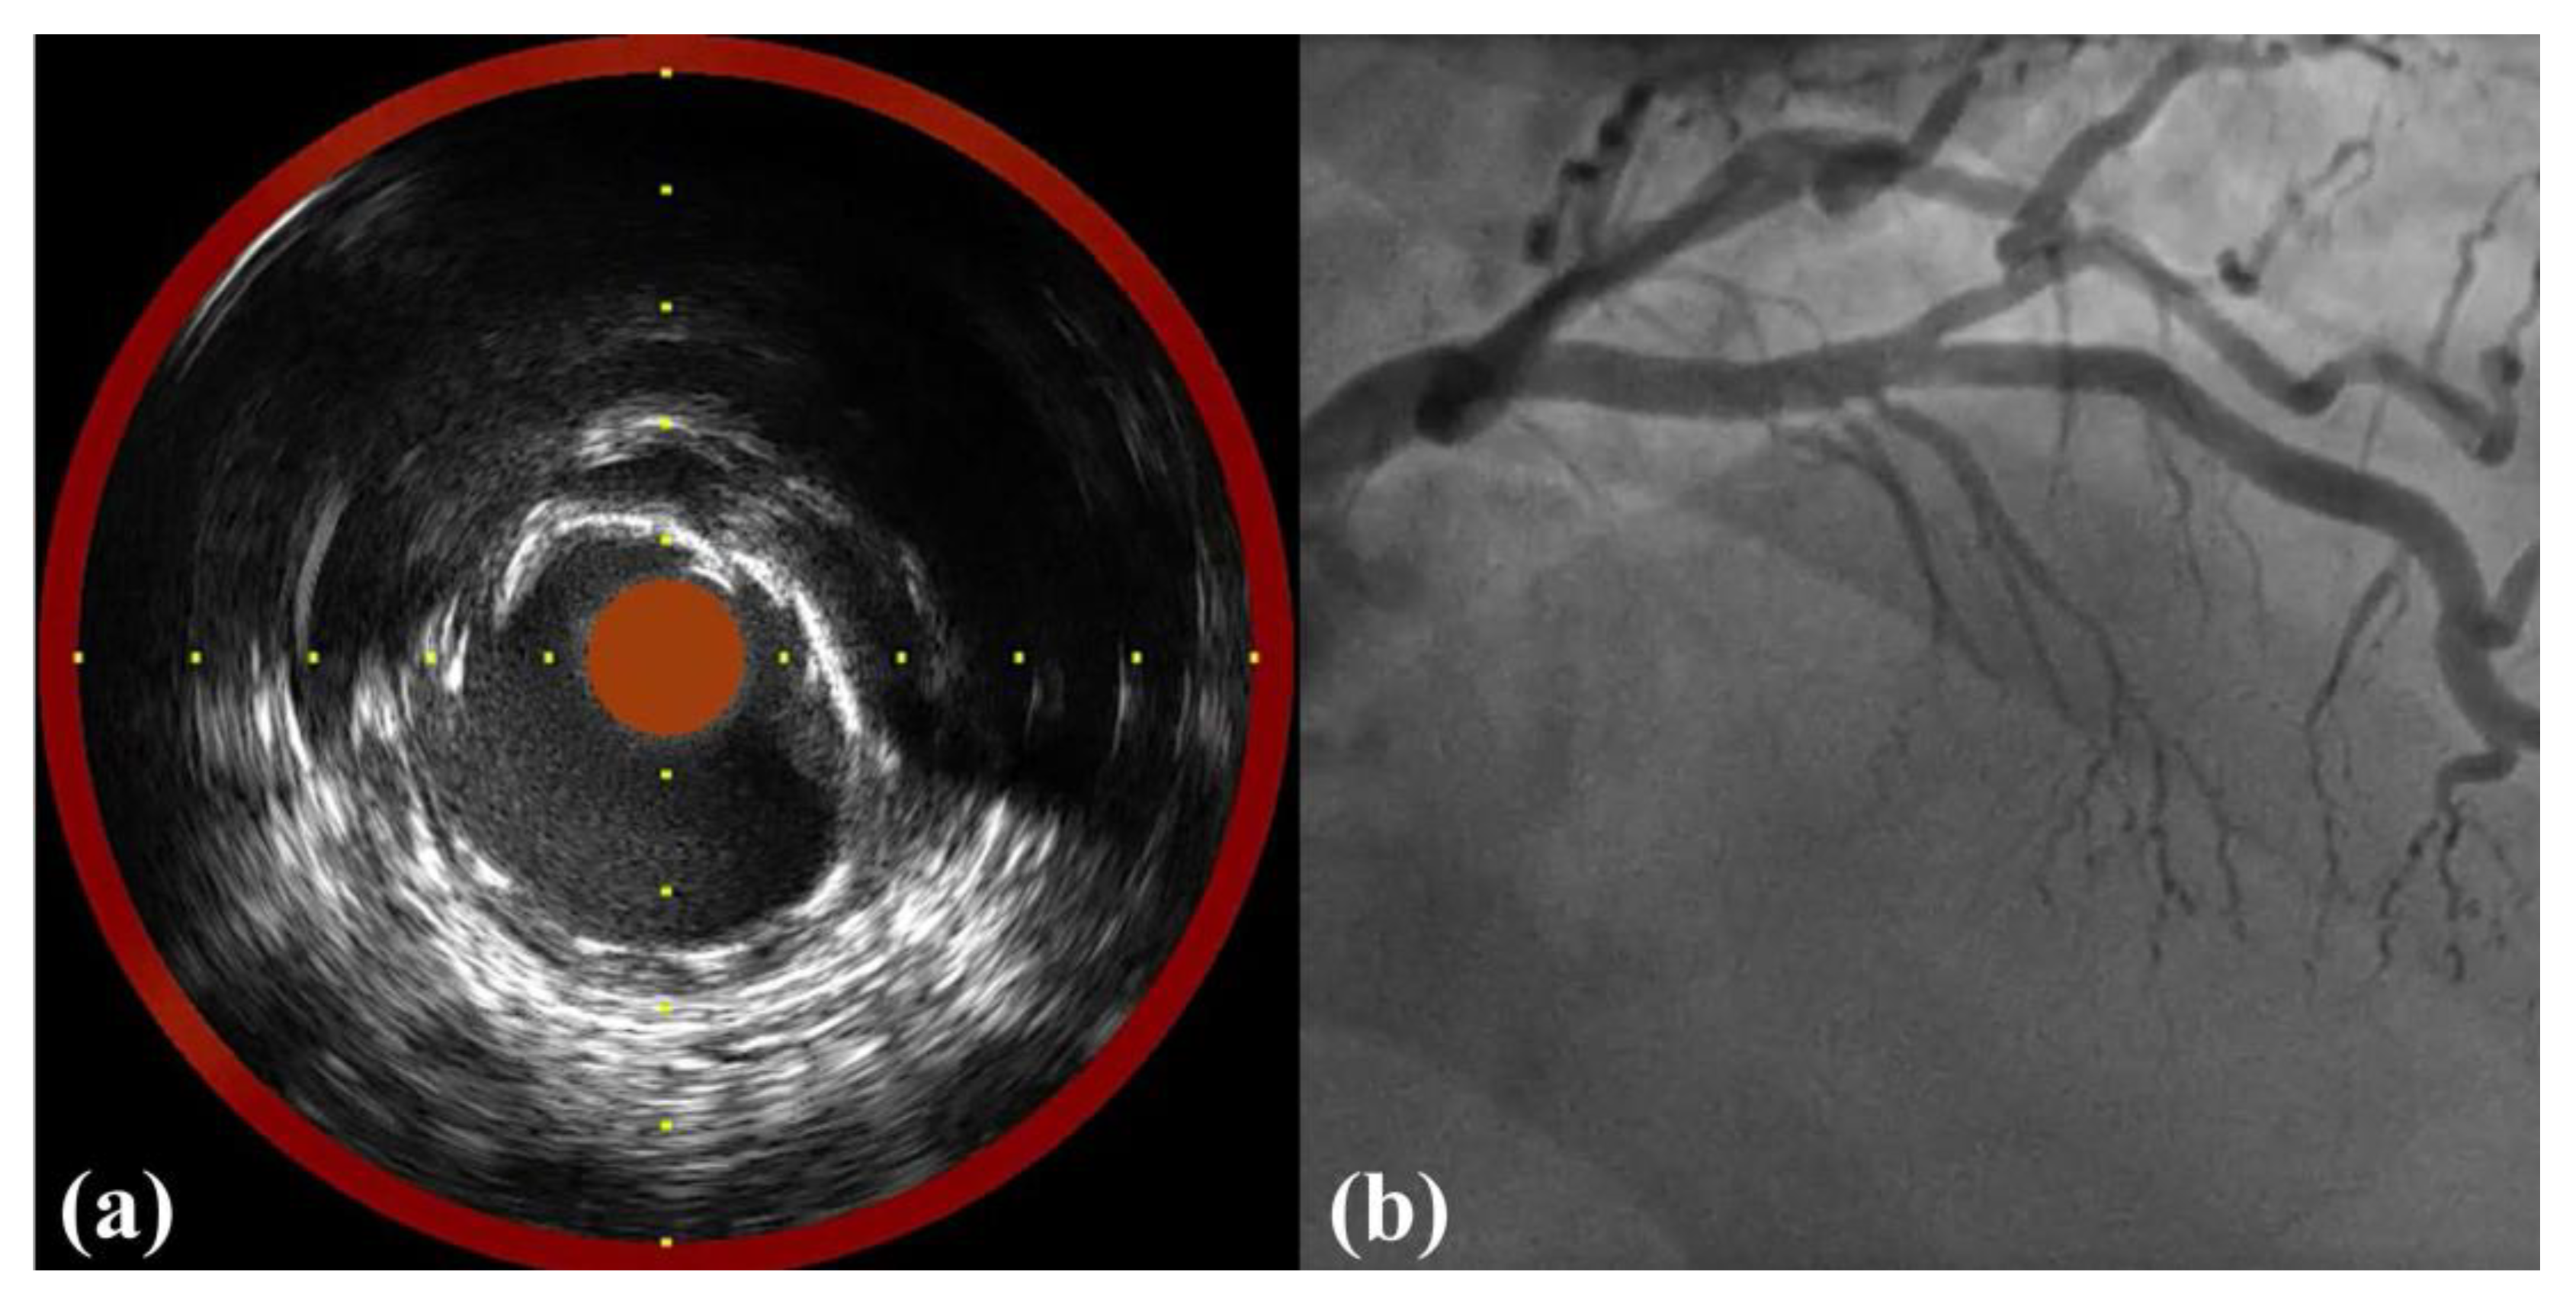

Near-Infrared Spectroscopy Intravascular-Ultrasound-Guided Intervention in Minimal Coronary Artery Stenosis: A Case Report

2. Case Report

| Profiles | Pre-PCI | Post-PCI |

|---|---|---|

| LCBI | 211 | 114 |

| maxLCBI4mm | 462 | 282 |

| Minimum dRD (mm) | 2.9 | 3.1 |

| Maximum dRD (mm) | 3.6 | 3.8 |

| dRA (mm2) | 8.8 | 10.0 |

| Minimum pRD (mm) | 3.3 | 3.5 |

| Maximum pRD (mm) | 4.0 | 3.9 |

| pRA (mm2) | 10.3 | 10.5 |

| Minimum MLD/MSD (mm) | 1.8 | 2.9 |

| Maximum MLD/MSD (mm) | 2.5 | 3.7 |

| MLA and MSA (mm2) | 3.7 | 8.9 |

| Area stenosis (%) | 61.2 | 13.2 |

| Lesion and stent length (mm) | 17 | 18 |